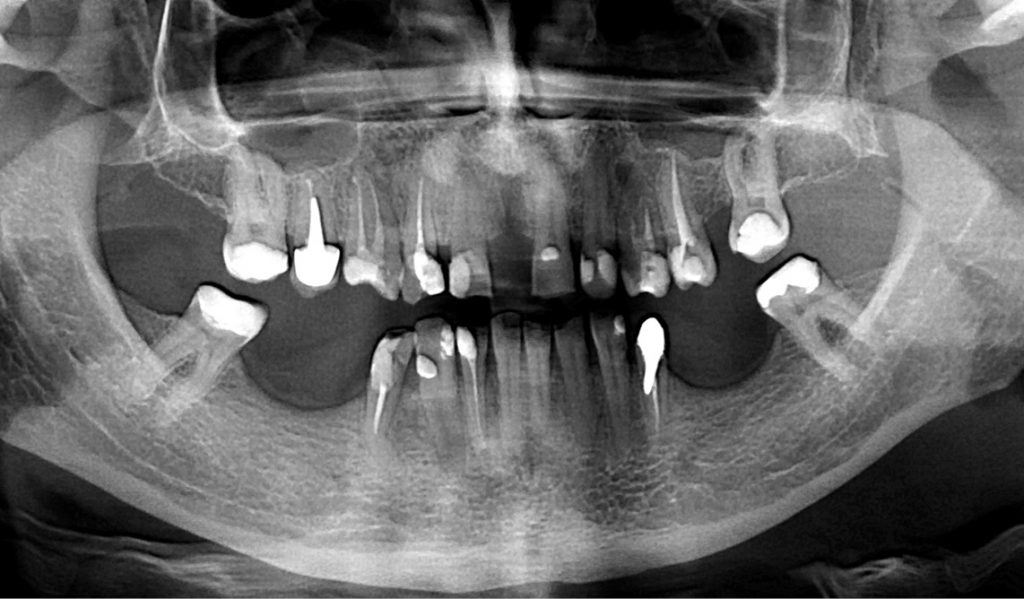

STRESZCZENIE: Rozpoznanie i zdiagnozowanie dilaceracji jest bardzo ważne w przypadku każdego zęba wymagającego leczenia kanałowego. Opracowanie mocno zakrzywionych kanałów korzeniowych stanowi wyzwanie dla lekarza endodonty. Powodzenie leczenia endodontycznego tej anomalii zależy od zastosowania odpowiednich instrumentów, a także od wiedzy i umiejętności klinicysty. W artykule zostały opisane przypadki własne pacjentów, u których zdiagnozowano dilacerację korzenia, przeprowadzono pierwotne oraz powtórne leczenie kanałowe zębów przedtrzonowych żuchwy z zakrzywieniem kanału trzeciego stopnia według Schneidera.

SUMMARY: The recognition and diagnosis of dilaceration is very important for any tooth requiring root canal treatment. The instrumentation of severely curved root canals is a challenge for an endodontist. The success of the endodontic treatment of this anomaly depends on the use of appropriate instruments, as well as on the knowledge and skills of a clinician. The article describes the authors’ own cases of patients diagnosed with root dilaceration who underwent the primary treatment and retreatment of root canals with the third degree of canal [...]